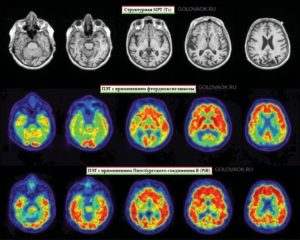

Диагностика и лечение

Первым этапом диагностики заболевания является доскональный опрос пациента с целью выявить беспокоящие его симптомы, общее состояние, порог мышления. Атрофические заболевания головного мозга предполагают обязательное проведение рентгенологического обследования, которое по слоям исследует мозговые доли, позволяет выявить наличие опухолей, гематом, очагов изменений.